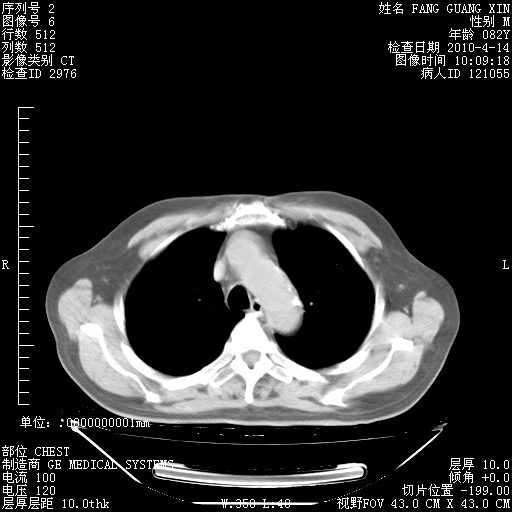

肺部CT平扫未见异常。